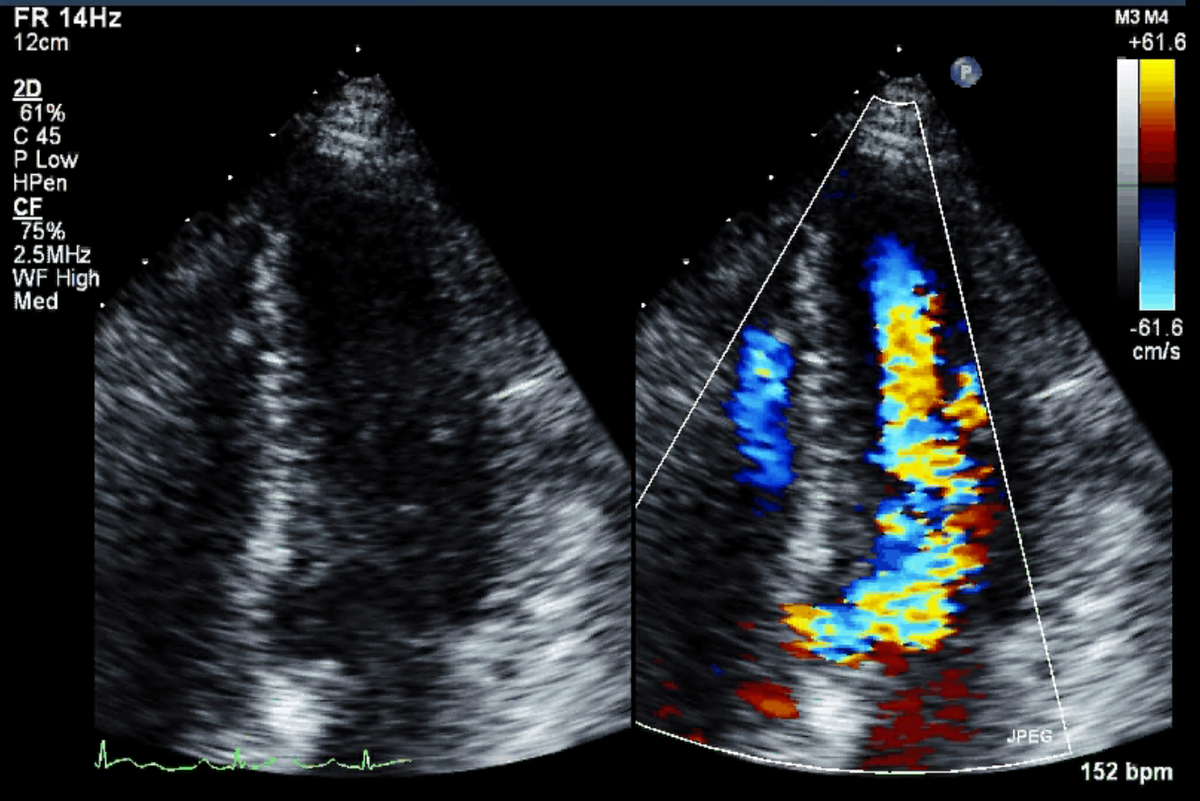

The Centre for AI, Data Science, and Imaging is redefining how cardiac care is delivered by combining cutting-edge artificial intelligence, advanced imaging, and data sciences to improve the diagnosis, treatment, and prevention of heart disease across British Columbia and beyond.

A patient’s geographical location should not determine the quality of care they receive. Through the use of AI and remote imaging technologies, the Centre strives to reach underserved communities, from rural and remote regions to long-term care homes and marginalized urban populations. With these tools, the earlier detection of heart disease, support for clinical decisions, and personalized care based on a patient’s genetics, imaging results, and environment are made possible.

The Centre’s team is passionate about understanding the heart and how its size, shape, function, stiffness, and contractility, combined with genomic and environmental data, can predict the risk for heart attacks, stroke, and arrhythmias. With this insight, clinicians can intervene earlier and tailor care more effectively. It has the talent, data, infrastructure, and visionary leadership to make this future a reality.